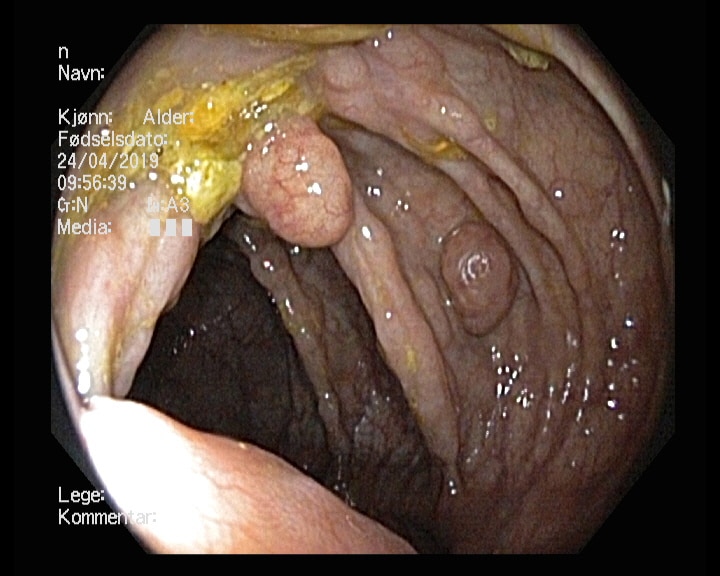

Tidligere frisk mann f.-33 som kom til koloskopi pakkeforløp pga magesmerter, endret avføring, Hb-fall tre enheter og pos hemofec. Trombocytopeni. Bedring etter oppstart PPI. Dag 1 dårlig tømt, kun distal skopi, men funn av stor polypp i venstre colon. Ved gastroskopi ulcerasjoner i tilheling. Dag 2 koloskopi med funn av atypiske polypøse lesjoner i mye av colon, både store og små. Bilde nr. 2 og 3: analt og oralt for sigmoideumvolvulus. Diagnose?